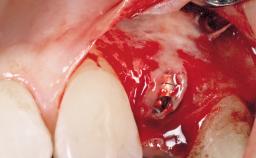

Immediate Placement of an Implant in a Maxillary Left Central Incisor Site

A 33-year-old female patient presented with an upper left central incisor that required extraction after a failed endodontic therapy. The tooth had been traumatized when the patient was a teenager and had undergone several endodontic treatments, including two apicectomy procedures. The patient was in good health and did not smoke. Clinical examination showed that the patient had a high lip line. In full smile, the gingival margins of the upper teeth were visible to the first molars. The gingival margins of central incisors 11 and 21 were only just showing. Examination of tooth 21 confirmed that the tooth was mobile and had hypererupted by 1 mm.

Placement Protocol Immediate implant placement

Socket Morphology Single-root socket

Socket Integrity Damage to one or more bone walls

Bone Volume Damage to one or more socket walls